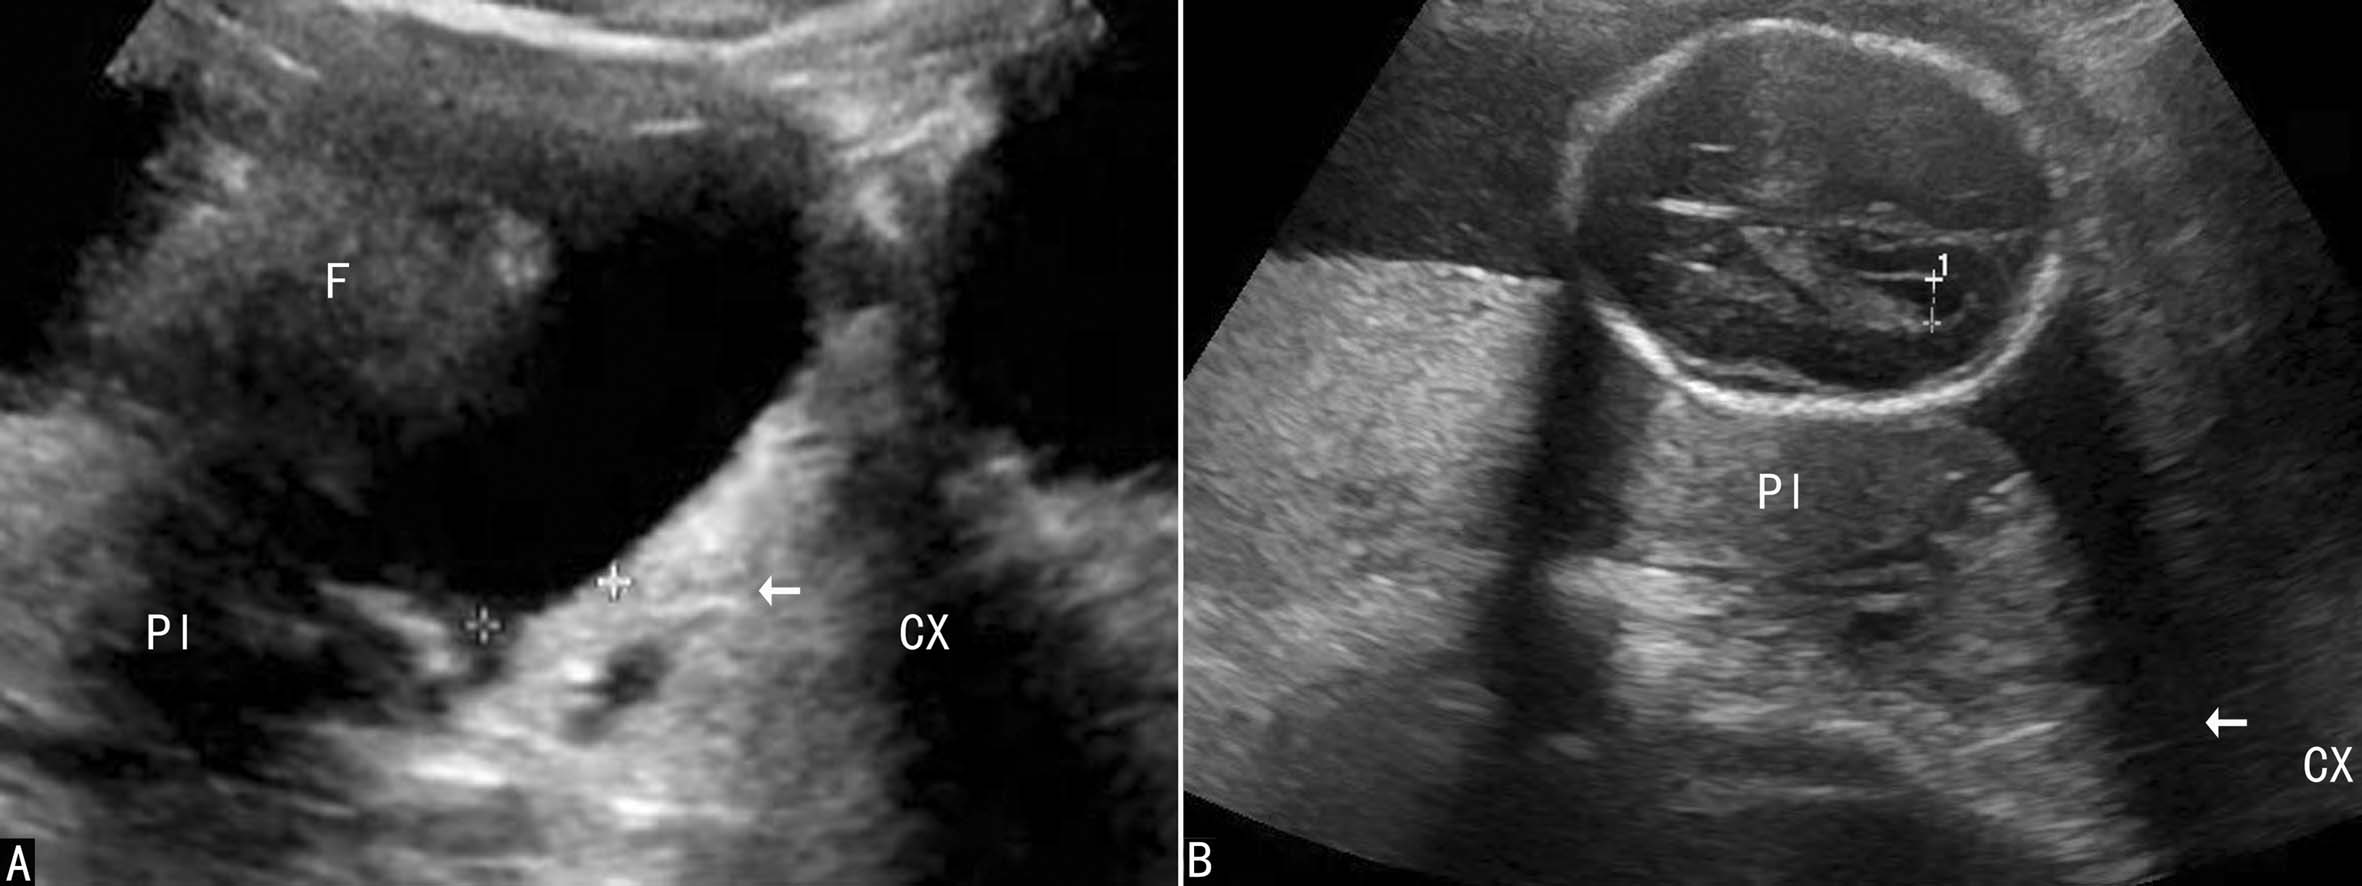

完全性:指胎盘组织完全覆盖宫颈内口(图1A)。

部分性:胎盘组织部分覆盖宫颈内口(图1B)。

边缘性:胎盘附着于子宫下段,边缘达到但未超越宫颈内口(图1C)。

适当充盈膀胱有助于宫颈内口辨认;扇扫或凸阵式探头检查利于子宫下段和宫颈内口的显示。中晚期妊娠时宫颈内口与羊膜腔最低点对应,可以显示对应宫颈管线状强回声。理想的膀胱充盈情况下,羊膜腔的最低点与胎儿先露部之间总能显示一定的距离,此处的羊膜囊称为前羊膜囊。前羊膜囊的存在对前置PL的显示非常有利。只要前羊膜囊内有PL显示,下缘至子宫颈内口的距离<2cm,如合并阴道流血,PLP诊断即可成立(图2A)。依据PL边缘与宫颈内口关系,可诊断边缘型(图2B)或完全型PLP(图2C、D)。由于2D-US均是在宫颈内口未开的情况下完成的,不宜做出部分型前置PL的诊断。

图2前置胎盘声像图AB

图2前置胎盘声像图CD